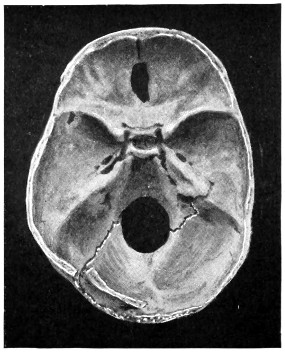

29 A and B. The base of the skull and the base as seen on transillumination 70, 71

50 A and B. The inner aspect of the skull and the same seen on transillumination 137